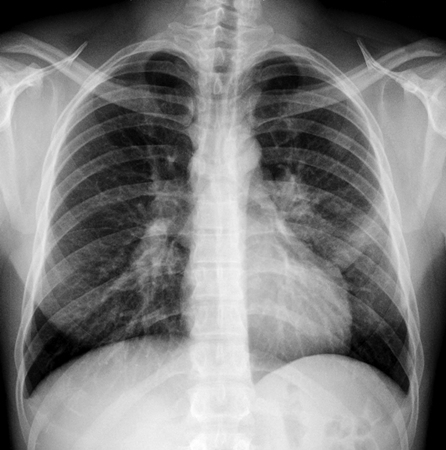

• x-ray of chest:

bilateral hilar adenopathy, right paratracheal adenopathy, pulmonary reticular opacities

pleural effusion and/or transient pulmonary infiltrate